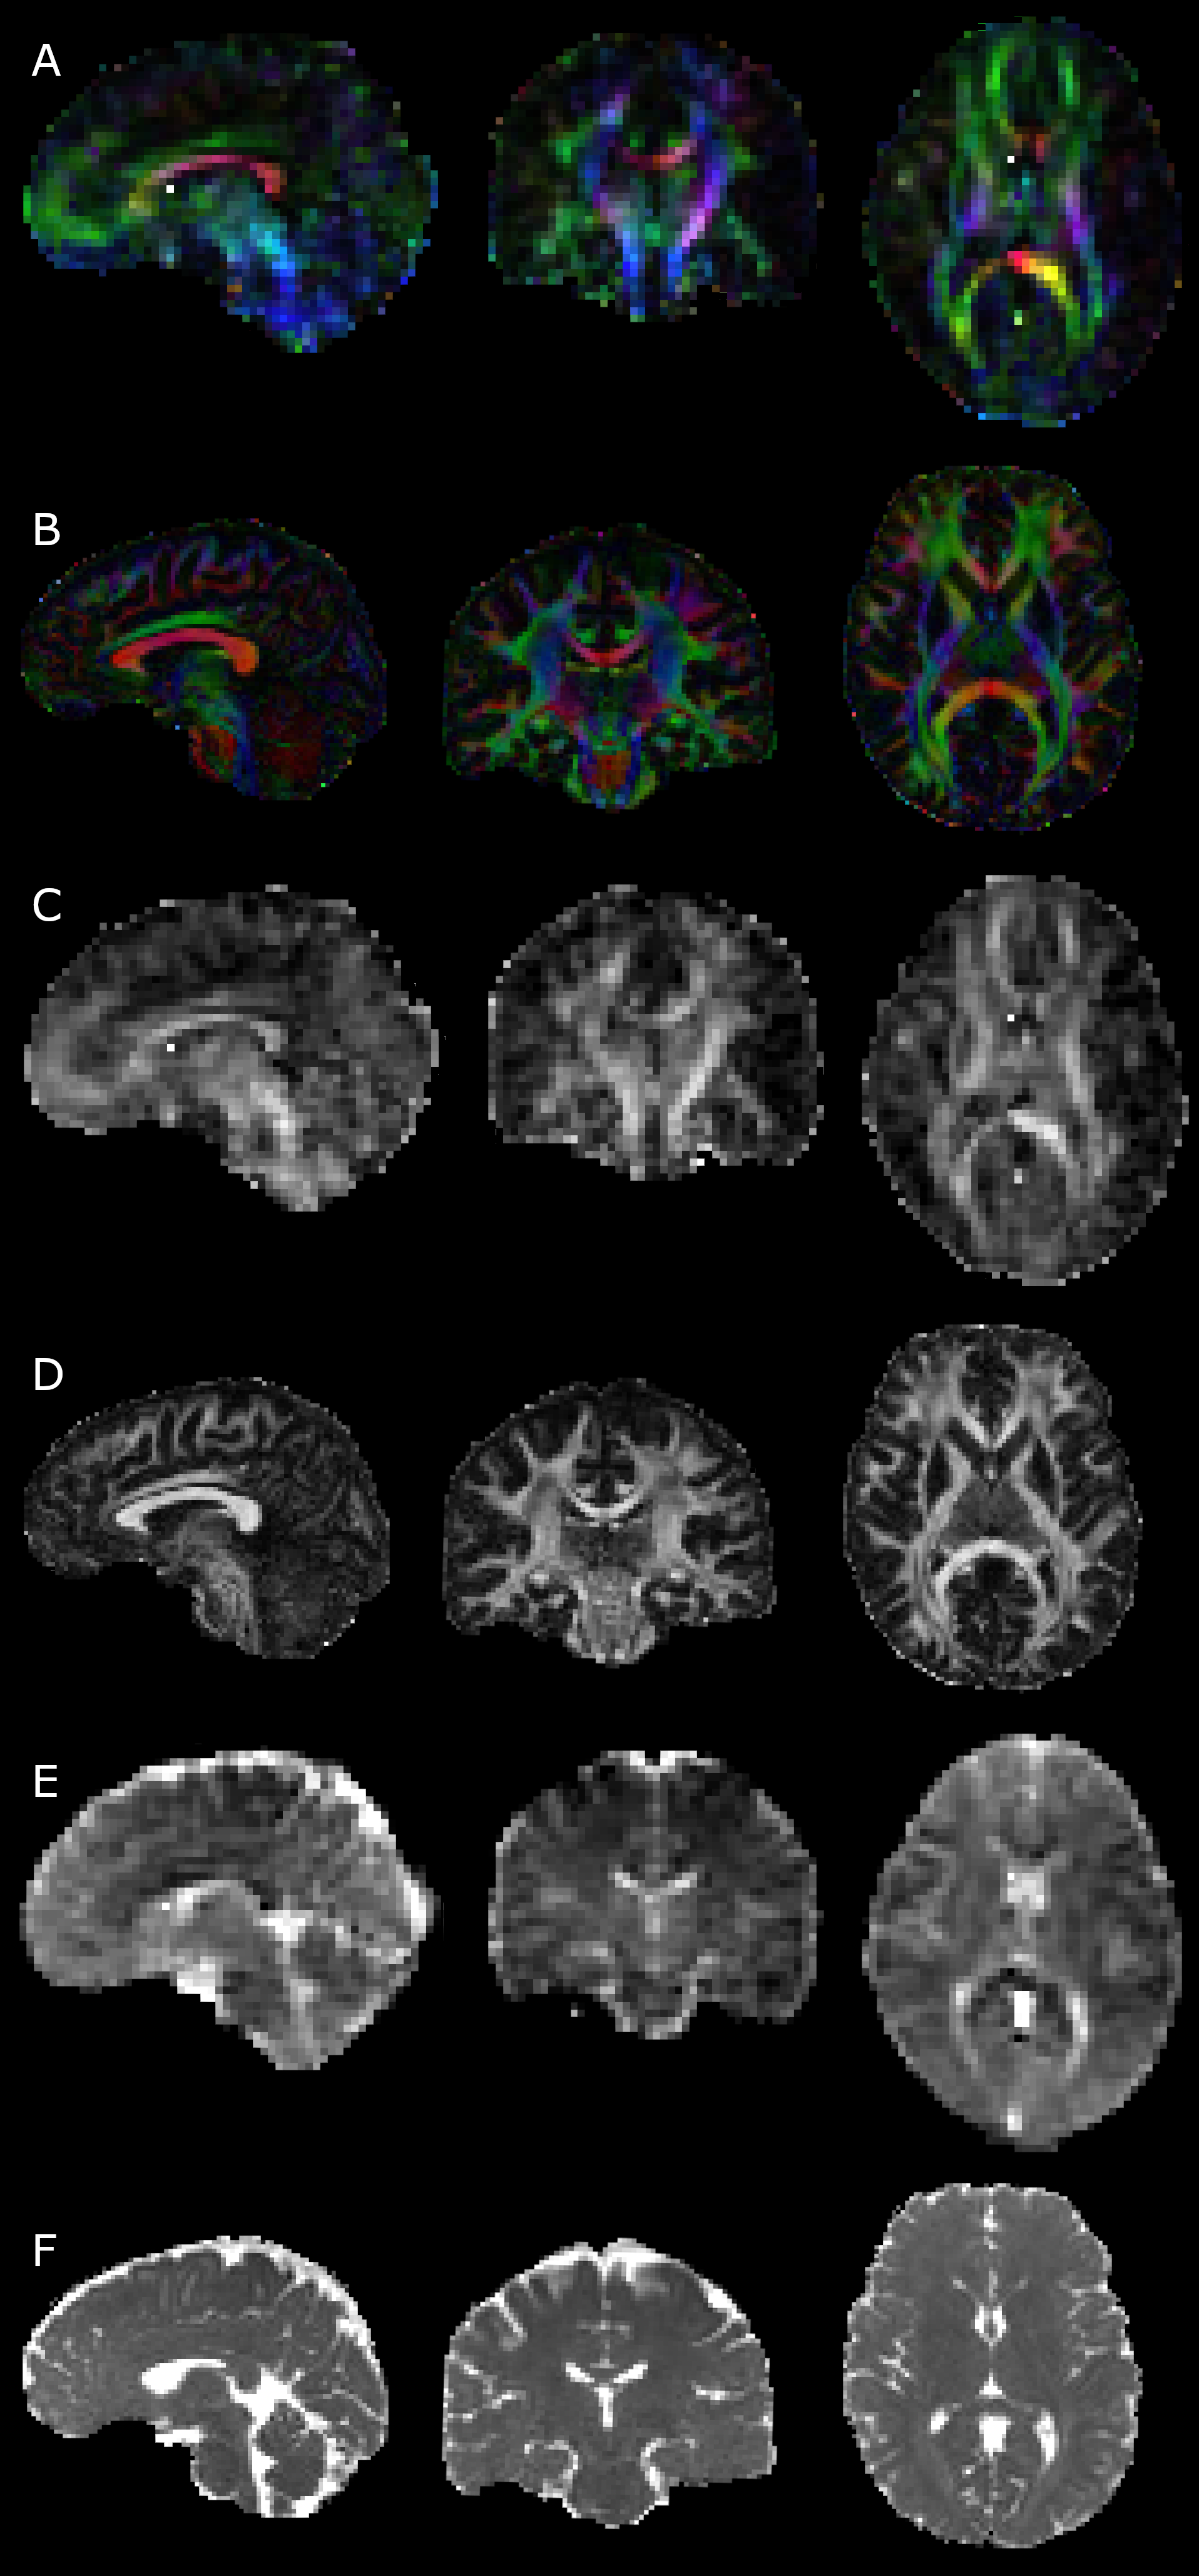

Diffusion measures at ULF visually corresponded with HF measures taken with small numbers of directions and a single shell. Diffusion encoded colour maps (Figure 2A, B) showed good agreement in major tracts, however anisotropic tissue further from the mid-sagittal axis plane (and hence isocentre) was not fully recovered, likely due to the high noise floor suppressing apparent fractional anisotropy. This was more visible in ULF FA maps directly (Figure 2C, D), where subcortical fibres were generally not observed, though were highly visible at HF. Imperfection and inconsistency in the shape of some major fibre bundles was observed, for example in the major forceps, where one side was measured to be more anisotropic than the other. Mean diffusivity maps (Figure 2E, F) showed generally good correspondence. Image quality and subsequent DTI measures and tracking quality was not found to vary substantially between individuals, and the results shown herein are a representative result of a compliant subject.

Refer to caption

Figure 2: Comparison of quantitative diffusion between high- (B,D, and F) and ultra-low-field (A, C, and E) measures obtained in the same subject in sagittal, coronal and axial planes. High field measures used 30 directions at b=1200 s/mm2times1200dividesecondmillimeter21200\text{\,}\mathrm{s}\text{/}{\mathrm{mm}}^{2}start_ARG 1200 end_ARG start_ARG times end_ARG start_ARG start_ARG roman_s end_ARG start_ARG divide end_ARG start_ARG power start_ARG roman_mm end_ARG start_ARG 2 end_ARG end_ARG end_ARG. A,B: diffusion encoded colour maps, weighted by FA. Distinct asymmetry is observed between left and right hemispheres in ULF data. This may arise from different spatial noise dependence, or from uncorrected diffusion encoding nonuniformity. C,D: fractional anisotropy - FA is noticeably lower in ULF measurements, again likely due to the elevated noise floor. Transverse WM is distinctly darker in FA measurements ULF than in HF, possibly due to the broad PSF and partial volume effects causing thinner bundles to appear more diffuse. E,F: mean diffusivity - shading is observed in ULF measurements, but otherwise there is good correspondence between HF and ULF measures.